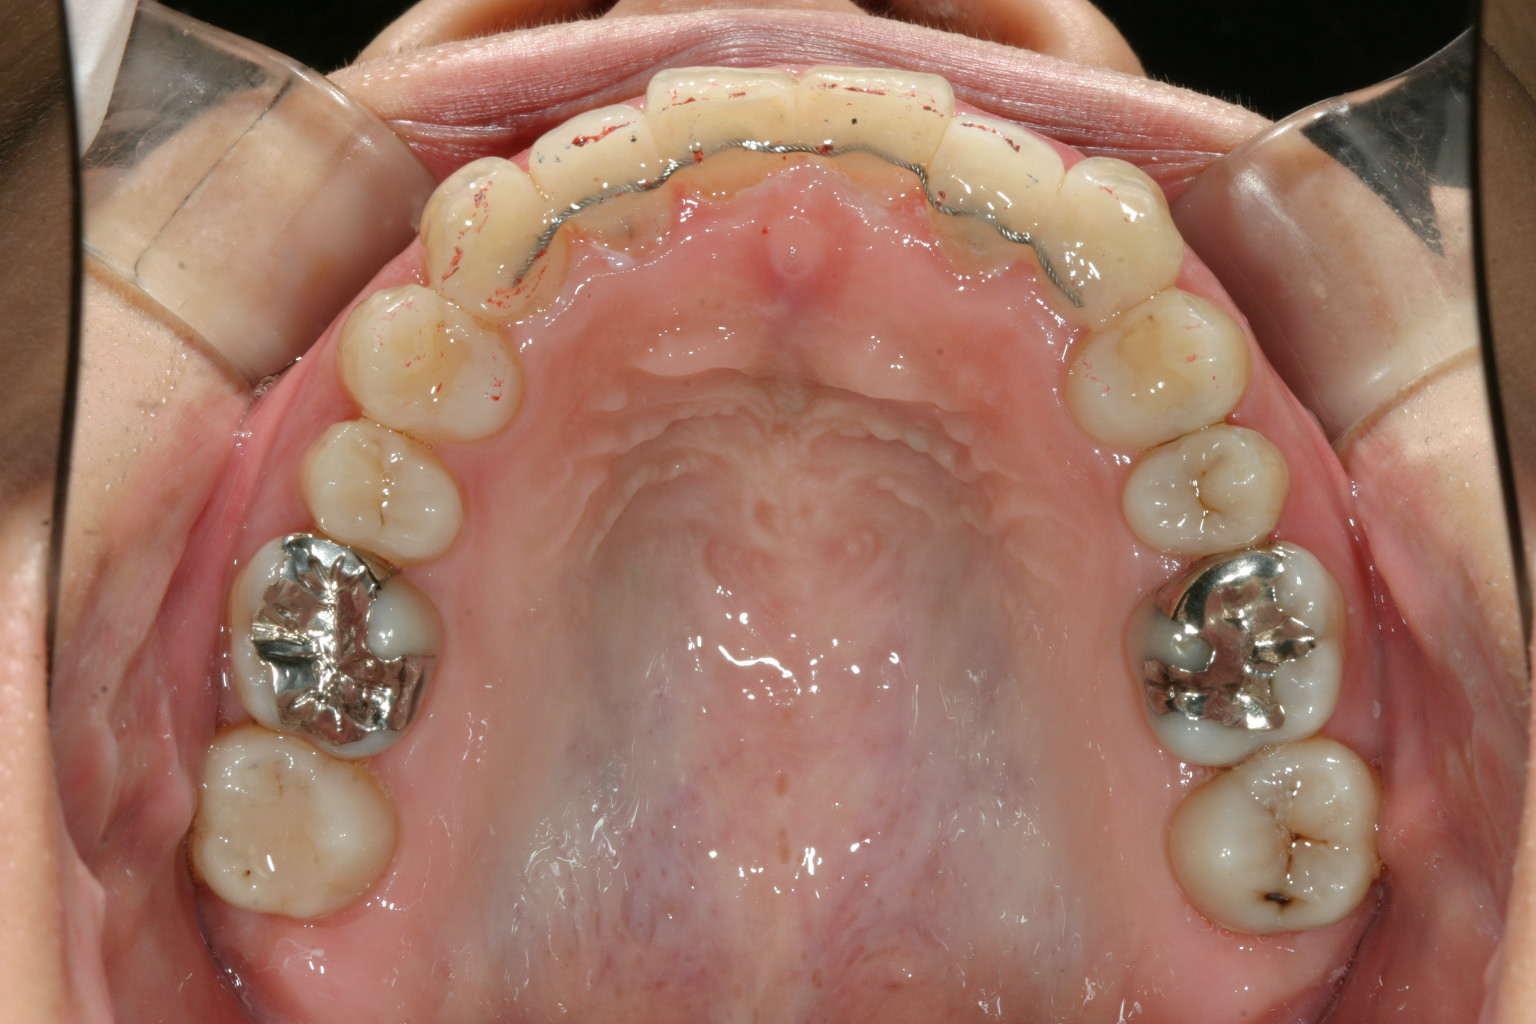

抜歯無しで綺麗に並びました。

先ずはいつものようにアーチを拡大し前歯が並ぶスペースを作る事により、でっぱも引っ込み

綺麗な歯列に改善します。

アーチの拡大だけでは出っ歯感がまだ残っている場合IPR(歯間部を少し削る)する事により

抜歯無しでかなりの確率で改善出来ます。